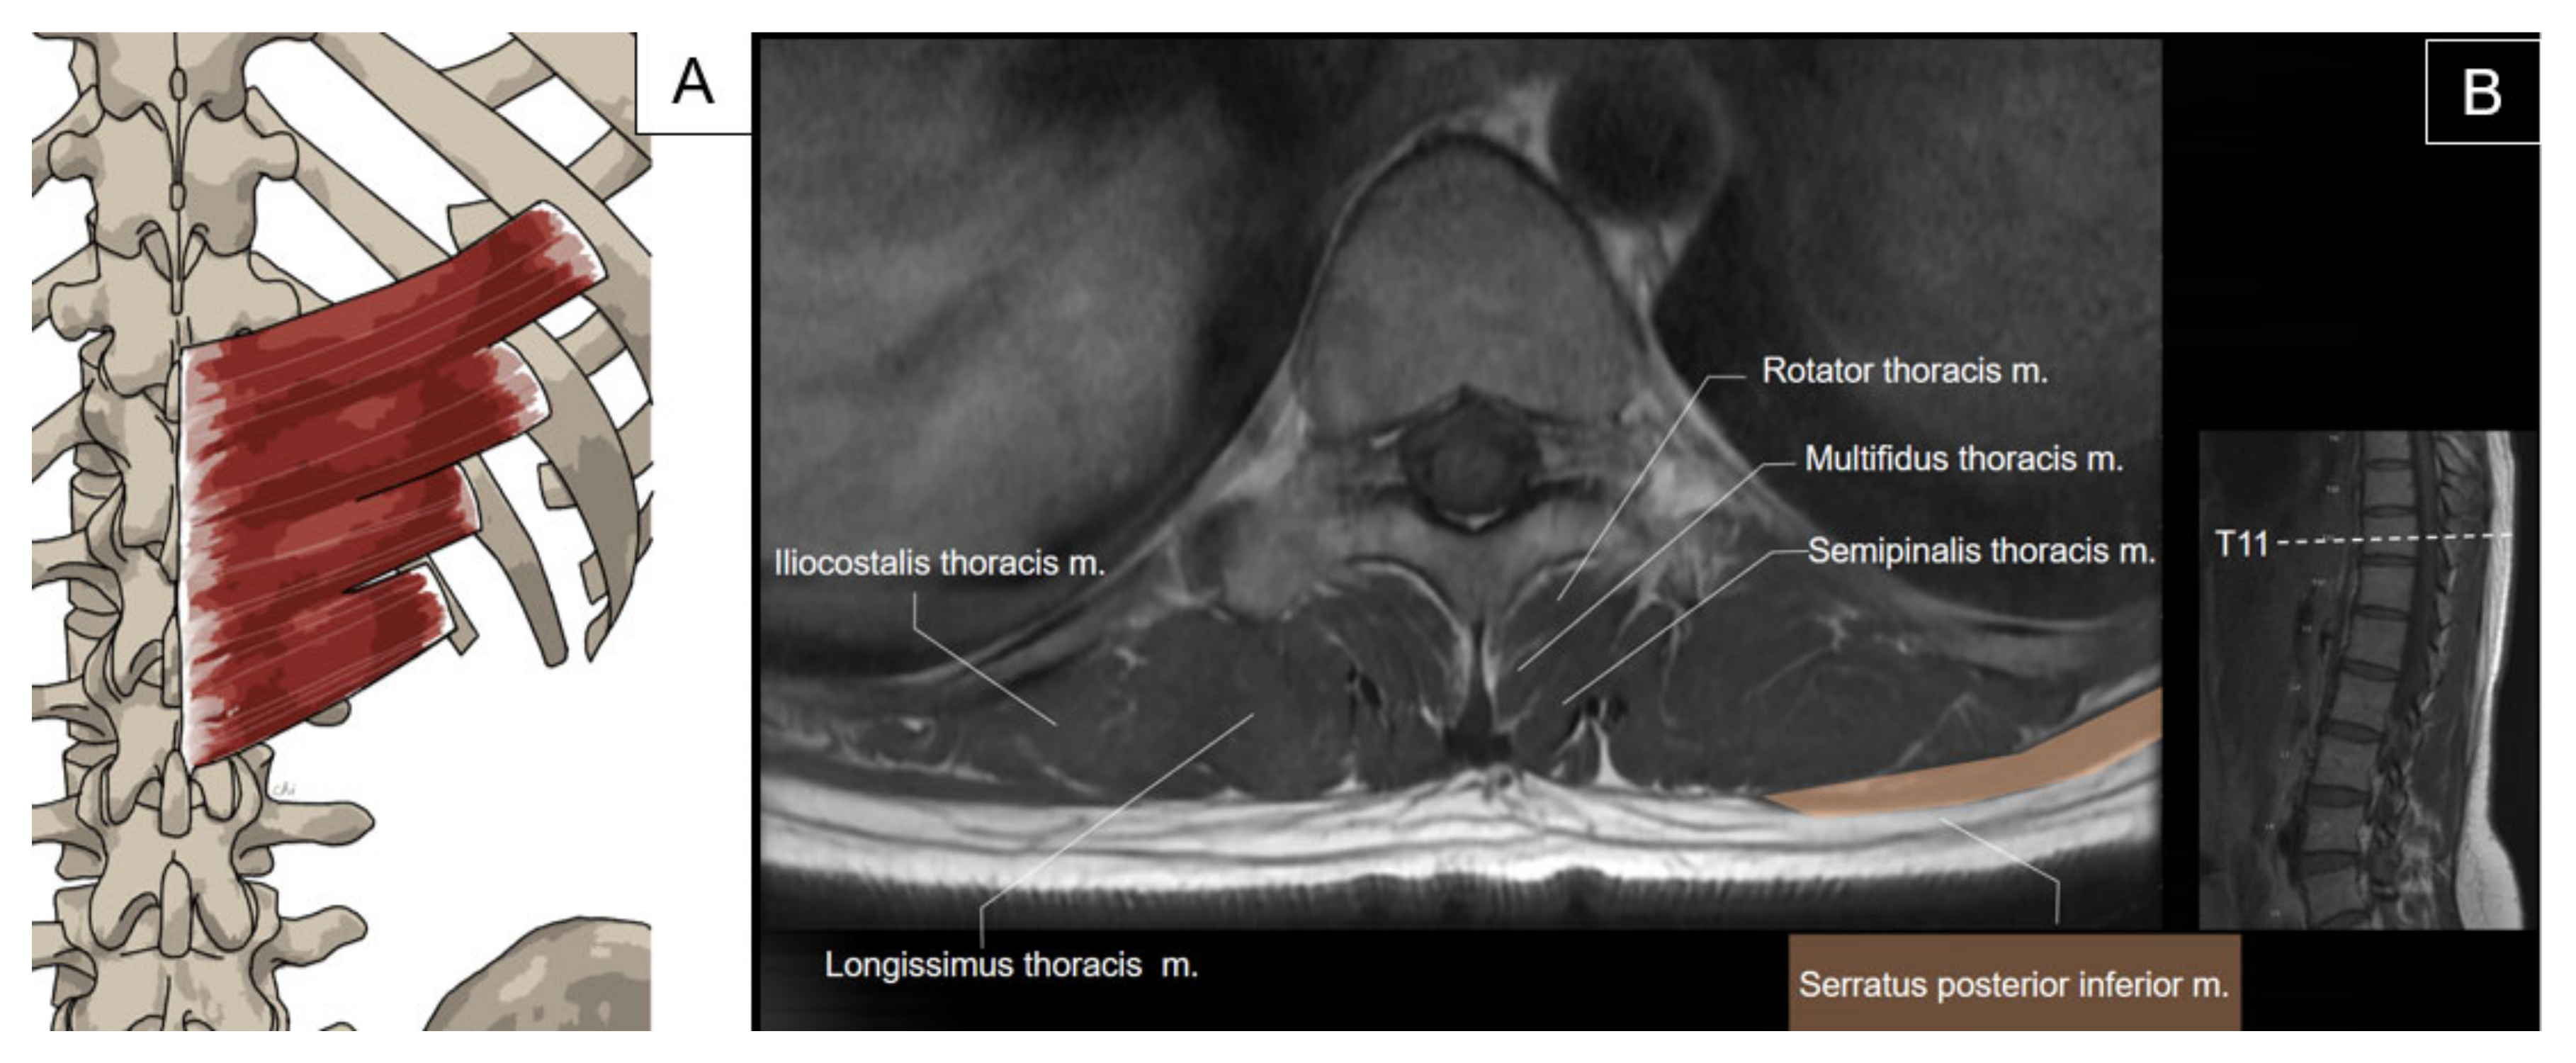

3.1. Serratus Posterior Superior/Inferior

3.1.1. Anatomy

3.1.2. Sonographic Scanning

3.1.3. Clinical Relevance